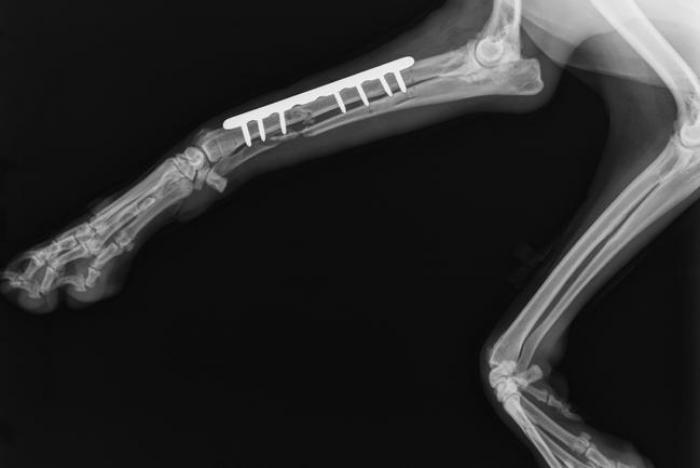

En esta formación te capacitas para dar solución a casos clínicos en traumatología y ortopedia veterinaria. Tratas los principios básicos, técnicas e instrumental para la colocación de los diferentes implantes; la resolución de las fracturas y las luxaciones de los huesos del miembro anterior y posterior. Aprendes a clasificar las fracturas de forma general y particular en cada hueso a tratar; los aspectos generales; el posicionamiento del paciente; los abordajes y los diferentes métodos de resolución.

- Interpretación radiográfica de las patologías traumáticas y ortopédicas

- Clasificación de las fracturas y su biodinámica

- Evaluación radiológica de la remodelación ósea